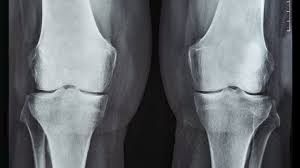

Understanding Knee Pain on Stairs

Knee pain on stairs can be a debilitating issue, affecting daily activities such as climbing stairs or even walking. To effectively manage and reduce knee pain, it is crucial to understand the underlying causes. There are several factors that can contribute to knee pain on stairs, including: